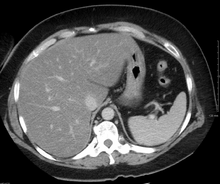

Radiography

On X-ray computed tomography (CT), the increased fat component will decrease the density of the liver tissue, making the image less bright. Typically the density of the spleen and liver are roughly equivalent. In steatosis, there is a difference between the density and brightness of the two organs, with the liver appearing darker.[12] On ultrasound, fat is more echogenic (capable of reflecting sound waves). The combination of liver steatosis being dark on CT and bright on ultrasound is sometimes known as the flip flop sign.